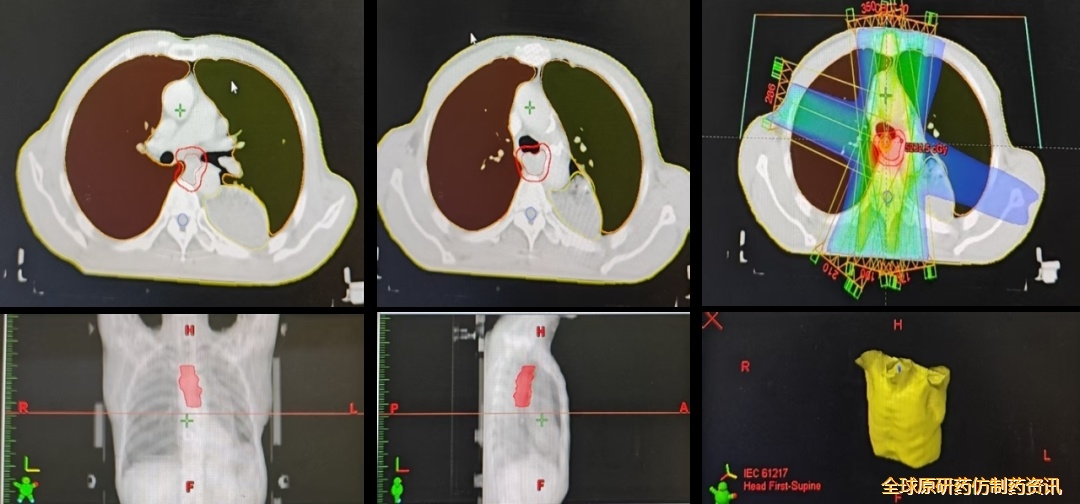

2024-07-23开始行后纵隔转移灶及左主支气管近端转移灶姑息性放疗,DT 50Gy/25F。

图3 患者接受灶姑息性放疗

图4 影像学检查结果对比

疗效评估:PR